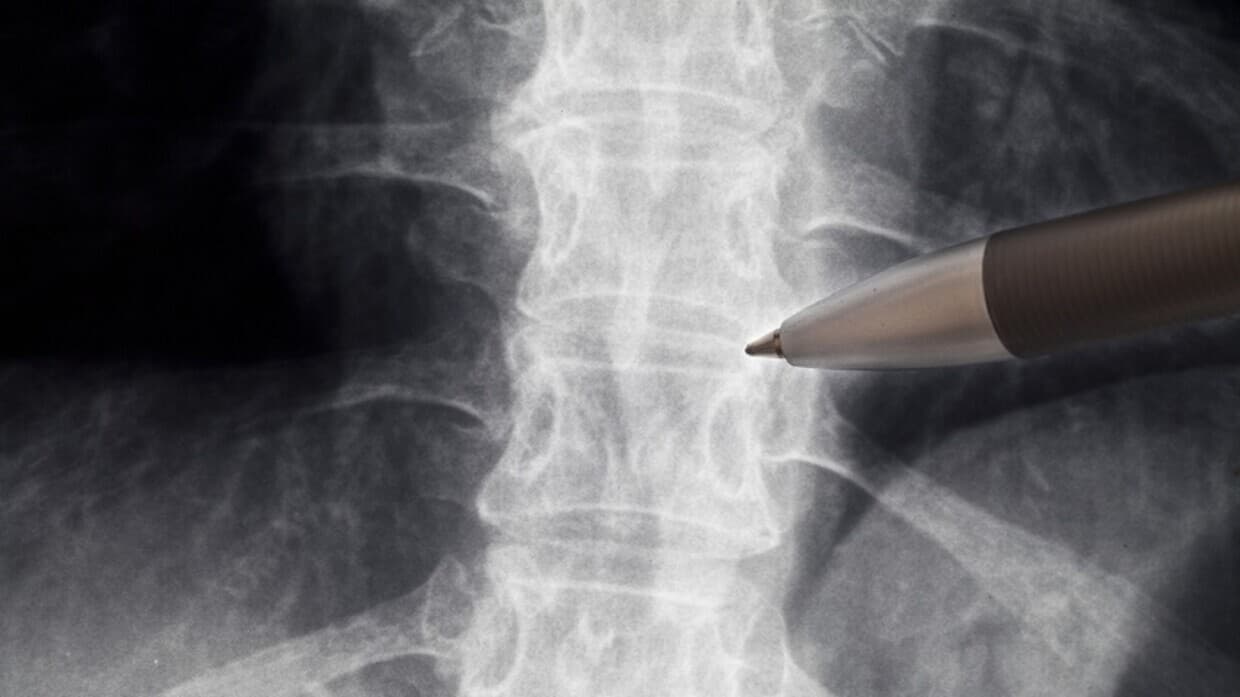

تیشک - نیشاندانی دڕکە پەتک

زاناکانی زانکۆی (Sirius) ڕووسی بۆ زانست و تەکنەلۆژیا، کاردەکەن بۆ پەرەپێدانی ڕێگەیەکی نوێ بۆ چارەسەرکردنی پچڕان یان برینداربوونی دڕکەپەتک لە بڕبڕەی پشتدا.

ڕاگەیێنراوی فەرمی: زانکۆی (Sirius) ڕووسی بۆ زانست و تەکنەلۆژیا ڕایگەیاندووە: زانایان لە زانکۆکەمان بە بەکارهێنانی (Trace amines) کاردەکەن بۆ پەرەپێدانی ڕێگەیەکی نوێ بۆ چارەسەرکردنی برینداربوونی دڕکەپەتک، ئەم شێوازە کلیلی پەرەپێدانی دەرمانی چارەسەری نوێیە بۆ نەخۆشەکان دوای برینداربوونێکی سەخت هیوایەک بەخۆیەوە دەبینێت بۆ چاکبوونەوەیەکی کاریگەرتر.

زانیاریی زیاتر: ئەم پڕۆژەیە پشتگیری لە دامەزراوەی زانستی ڕووسیا وەرگرتووە، لە چوارچێوەی بەرنامەی دەوڵەتی ڕووسیا بۆ گەشەپێدانی زانستی و تەکنەلۆژیی جێبەجێ دەکرێت. ڕووسیا لە نێو وڵاتانی ئەوروپادا لە پلەی دووەمدایە بۆ ئەم جۆرە ڕووداوانە.

ئەوەی پێویستە بیزانیت: شکانی بڕبڕەی پشت یان برینداربوونی دڕکەپەتک لەکاتی تووشبوون بە ڕووداوی سەخت نزیکەی 26%ی کۆی برینەکانی جەستەی مرۆڤ پێکدەهێنێت.

پەرەپێدانی چارەسەر بۆ ئەو جۆرە برینانە پێویستە، چونکە بەهۆی هەستیاریی ئەندامەکە لەوانەیە کاریگەری نەرێنی زۆری لێبکەوێتەوە، لەوانە ئاڵۆزییەکان لە سیستمەکانی دیکەی جەستەدا، وەک دڵ، خوێنبەرەکان، کۆئەندامی هەناسەدان و سیستمی هەرس.